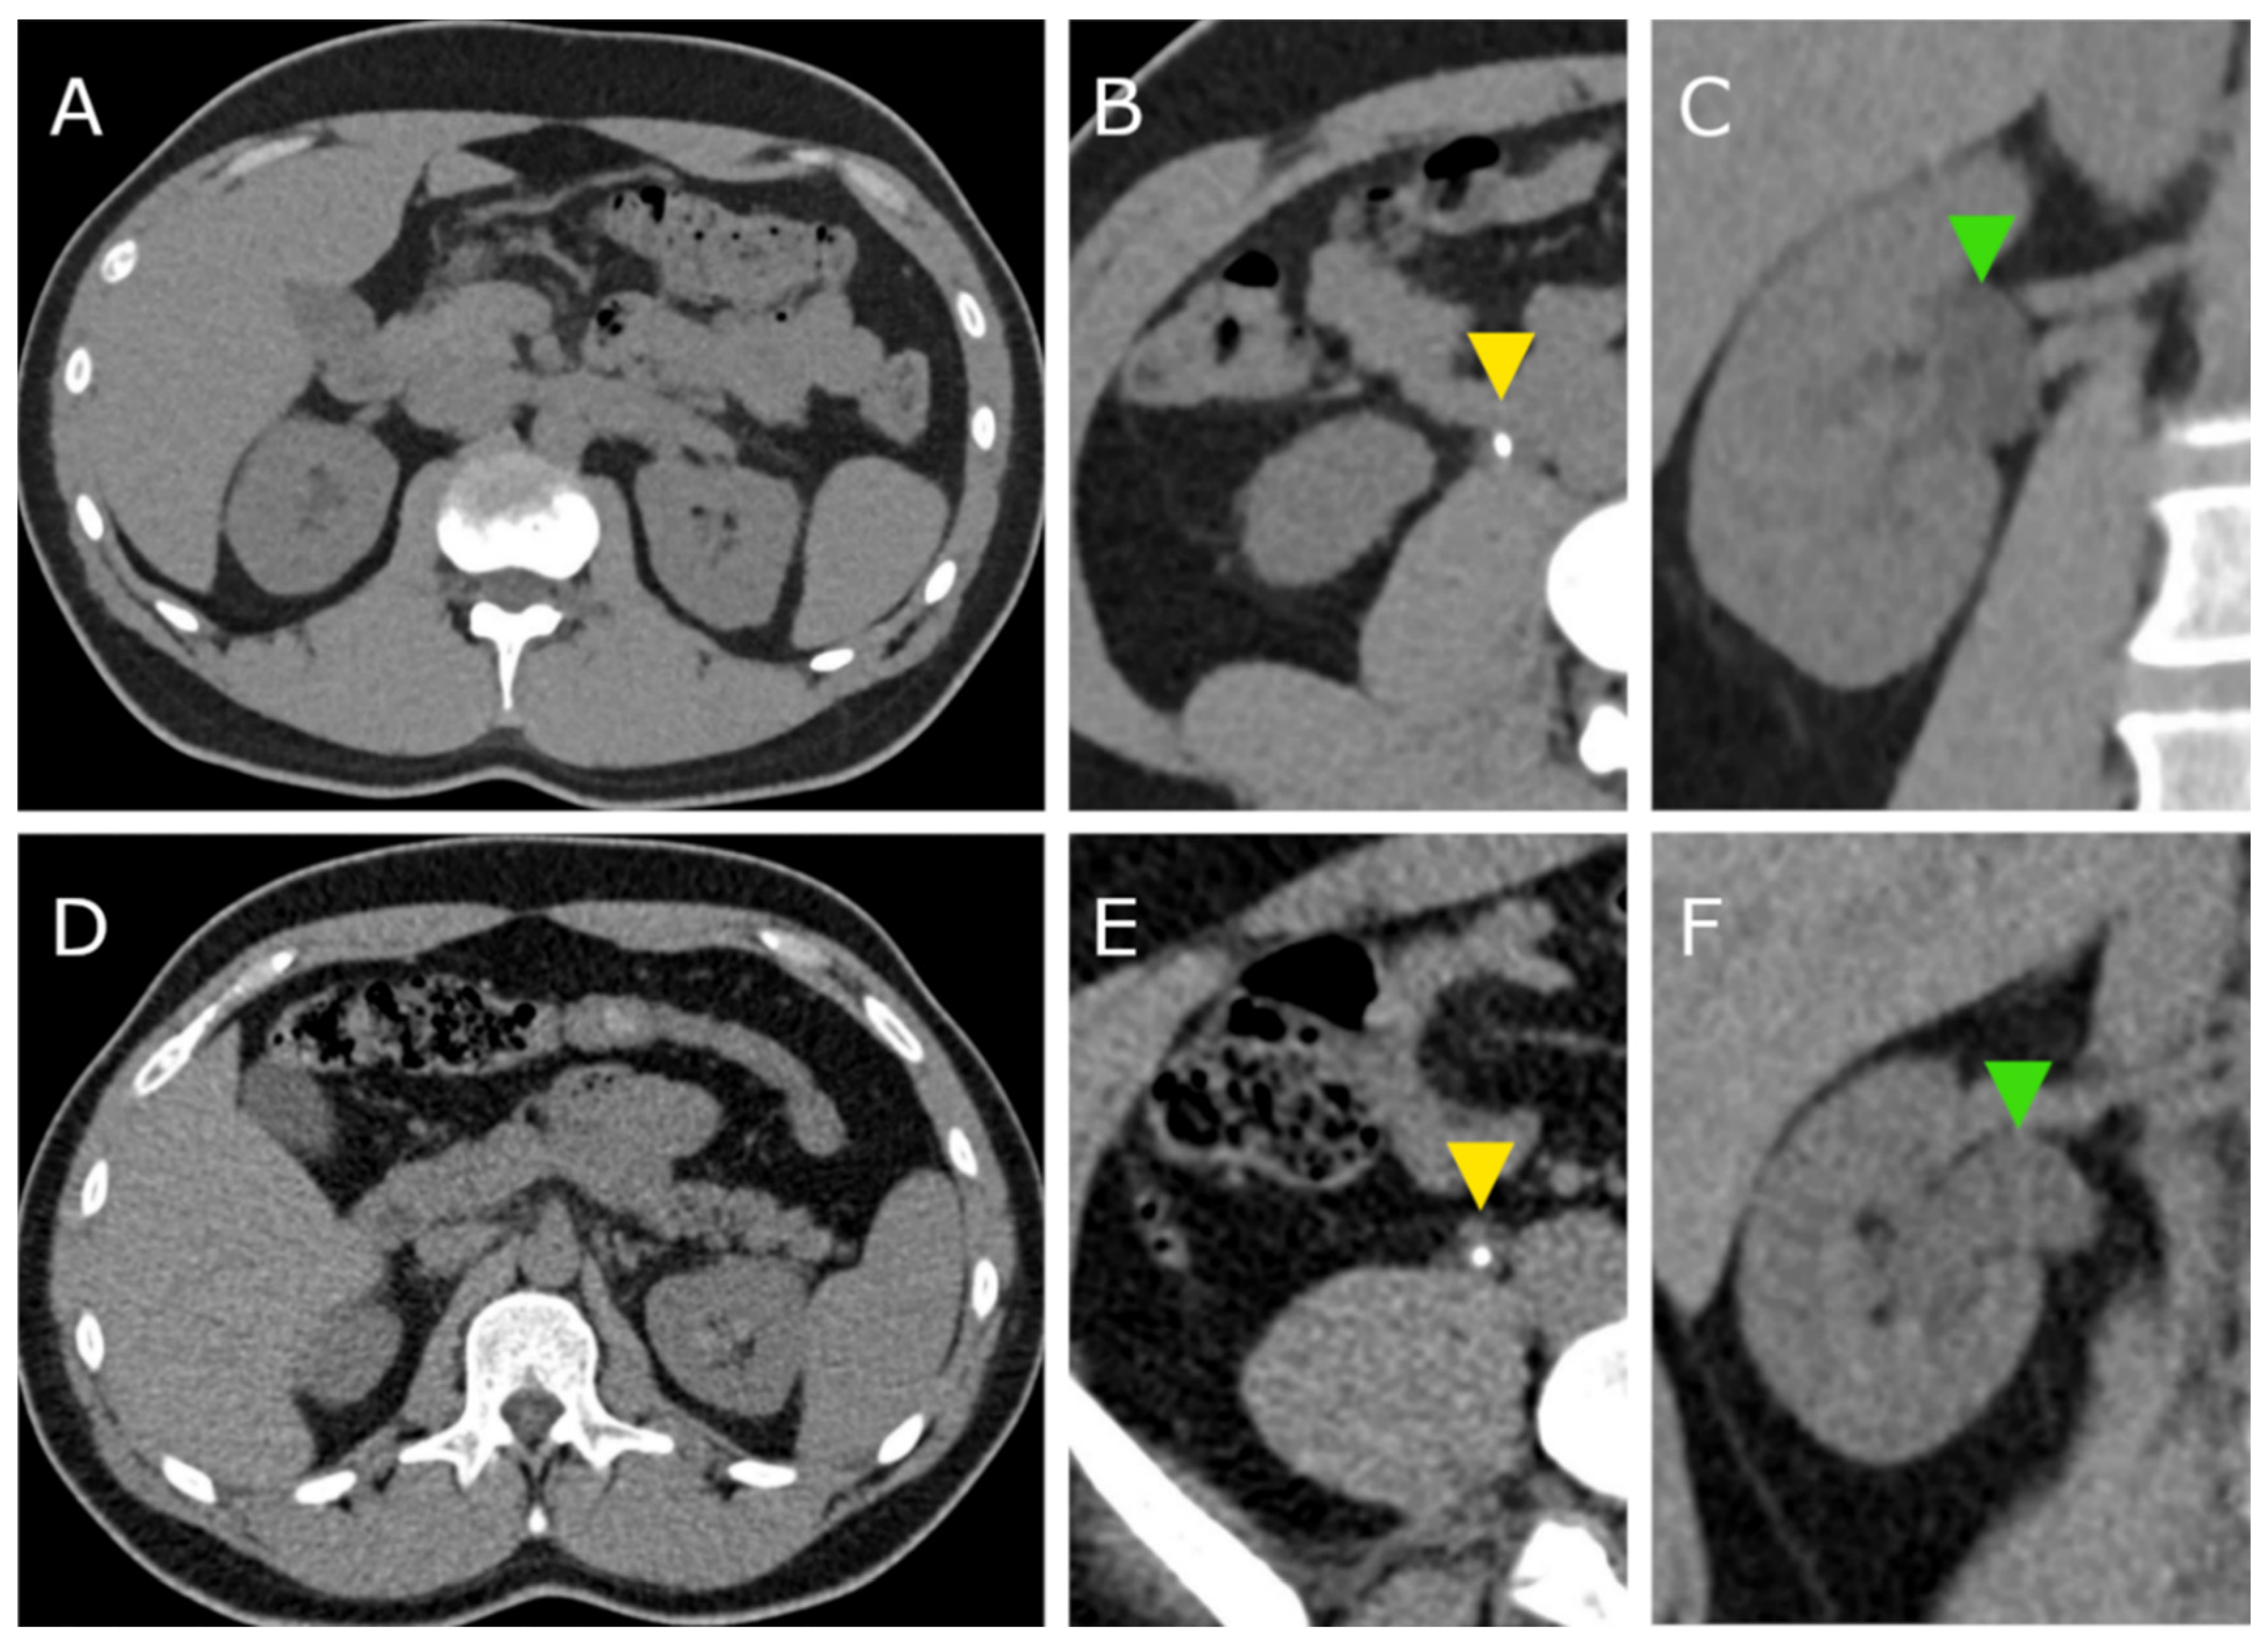

In total, CT scans of 63 patients were included in the analysis. Thirty-one patients (16 female, 15 male) were examined with the PCCT and 32 patients (11 female, 21 male) were examined with the S40. Figure 1 exemplarily shows CT images of both scanners.

Figure 1. CT images acquired with the photon counting CT (PCCT, AC) and with the standard CT (S40, DE). Yellow arrowheads (B,E) indicate ureter stones in both patients. Green arrowheads (C,F) point to the dilated renal pelvis due to the ureter obstruction.